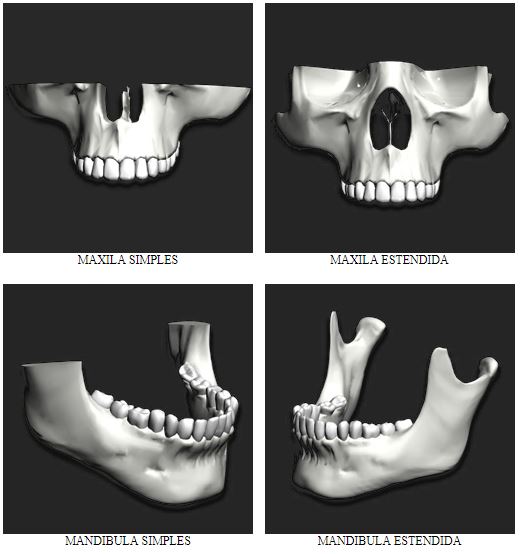

Tipos de protótipos:

.